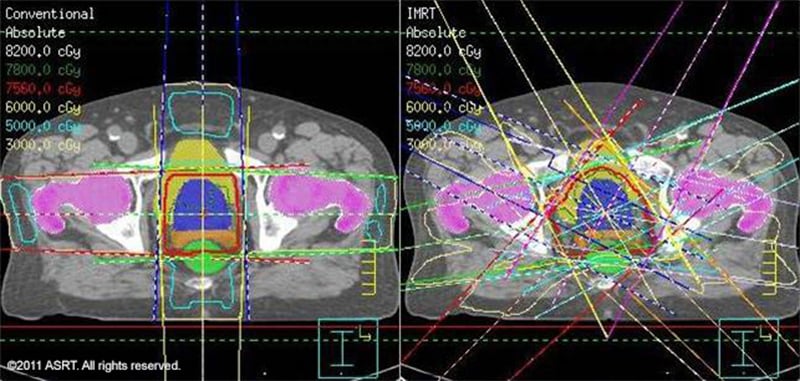

Radiation therapy is the primary tool to target tumors inside patients’ bodies. As the radiation strikes human tissue, it produces highly energized ions that gradually shrink and destroy the nucleus of malignant tumor cells. However, it’s targeted so it doesn’t damage the surrounding tissue.

Radiation Therapy / Image © ASRT

Radiation therapy